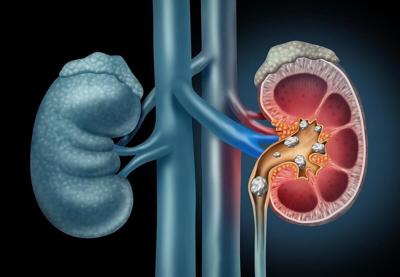

Kidney stones are hard objects that form inside the organ from chemicals in urine. These stones can cause pain both inside the kidney and as they pass out of the body during urination, according to the National Kidney Foundation.